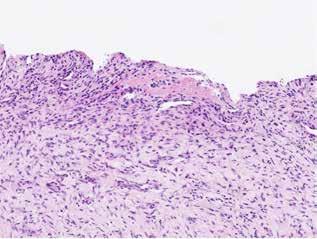

deltaa@ddeltaa--rengoering d dk

www.delta-rengoering.dk

Hvis jobannoncen bliver indrykket på både Dentaljob.dk og i Tandlægebladet, får du 50 % rabat på annoncen i bladet

BAGGRUND – Centralt kæmpecellegranulom (Central giant cell granuloma – CGCG) er en sjælden, godartet læsion, som nærmest udelukkende er lokaliseret til kæberne. Det har kliniske, radiologiske eller histologiske ligheder med flere andre intraossøse læsioner. Ætiologien er stadig ukendt, men det viser sig, at genetiske mutationer er associeret med forekomsten af CGCG.

PATIENTTILFÆLDE – Tre drenge i alderen fem og seks år blev alle diagnosticeret med og behandlet for større CGCG-læsioner med få måneders mellemrum på Tand-, Mund- og Kæbekirurgisk Klinik, Aarhus Universitetshospital.

KONKLUSION – Det er yderst relevant at følge børn med spontant og tidligt tandtab i kommunal tandpleje. Ved mistanke om patologiske forandringer henvises til hurtig udredning og diagnostik i hospitalsregi for at klarlægge diagnose og minimere skader på blivende tandanlæg og omkringliggende strukturer.

EMNEORD Central giant cell granuloma | giant cell lesions | jaw neoplasm | benign bone diseases

CHRISTIAN LIND AXELGAARD, specialtandlæge i tand-, mund- og kæbekirurgi, Speciialklinik for kæbekirurgi, Silkeborg

KIMIE BOLS ØSTERGAARD, tandlæge i videreuddannelse til specialtandlæge i tand-, mund- og kæbekirurgi. Kæbekirurgisk Afdeling, Aalborg Universitetshospital

SVEN ERIK NØRHOLT, klinisk professor, specialtandlæge i tand-, mund- og kæbekirurgi, ph.d., overtandlæge, Afdeling for Tand-, Mund- og Kæbekirurgi, Aarhus Universitetshospital, og Sektion for Kæbekirurgi og Oral Medicin, Institut for Odontologi og Oral Sundhed, Aarhus Universitet

PER JOHAN SIXTEN BLOMLÖF, overtandlæge, docent, ph.d., specialtandlæge i tand-, mund- og kæbekirurgi, Afdeling for Tand-, Mund- og Kæbekirurgi, Aarhus Universitetshospital

STEEN BÆRENTZEN, overlæge, Patologiafdelingen, Aarhus Universitetshospital